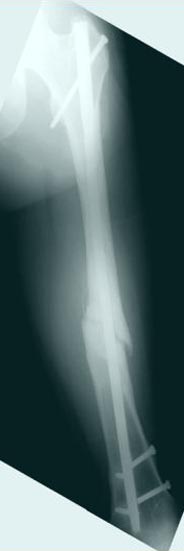

Снимки представлены: 1 мес; 3 мес; 1 год; 2 года, предоперационные и ротационная КТ грамма

Деформация:

Вальгус- 17 градусов

Рекурватум 5 градусов

Укорочение 2.5см

Ротационно 22 градусов внутренная

Смещение диафиза по поперечнику 75%